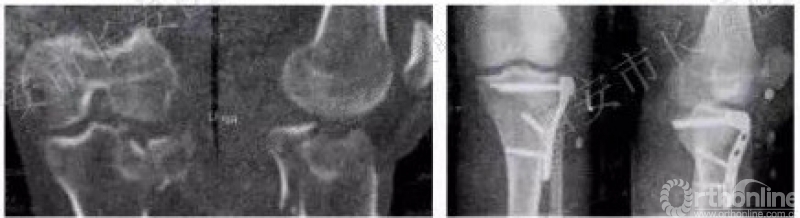

腓骨头上入路2

2012年储旭东

该方法:直接暴露外侧并后外部分。适用于41B2.1x或u并t,41B3.1x或u并t。

原文:冰冻成人膝关节10个。12例胫骨平台后外侧骨折行后外侧踝部暴露、复位固定。OA为9.43-14.92mm,平均12.97±1.83mm,膝关节在0度时外侧副韧带紧张,OB为4.87±0.33mm;屈膝时OB随外侧副韧带松弛而增大,屈膝60度时最为松弛,向后侧牵拉外侧副韧带同时稍内旋胫骨可完整显露后外侧踝。

腓骨头上入路3

2015年

该方法:直接暴露外侧并后外部分。适用于41B2.1t或x、41B3.1t或x。

原文:7例胫骨平台骨折经腓骨前外侧入路治疗。侧卧位,膝关节屈曲60°.LCL后退,将钢板向后放置。

原文:解剖5例新鲜和10个膝关节标本:腓骨头顶端至髁突表面的平均距离为12.2±1.6mm。PL平台与FCL之间的横向距离6.7±1.1mm.膝关节屈曲至60°,FCL处于最放松位置,距离增加到21.1±3.0mm。